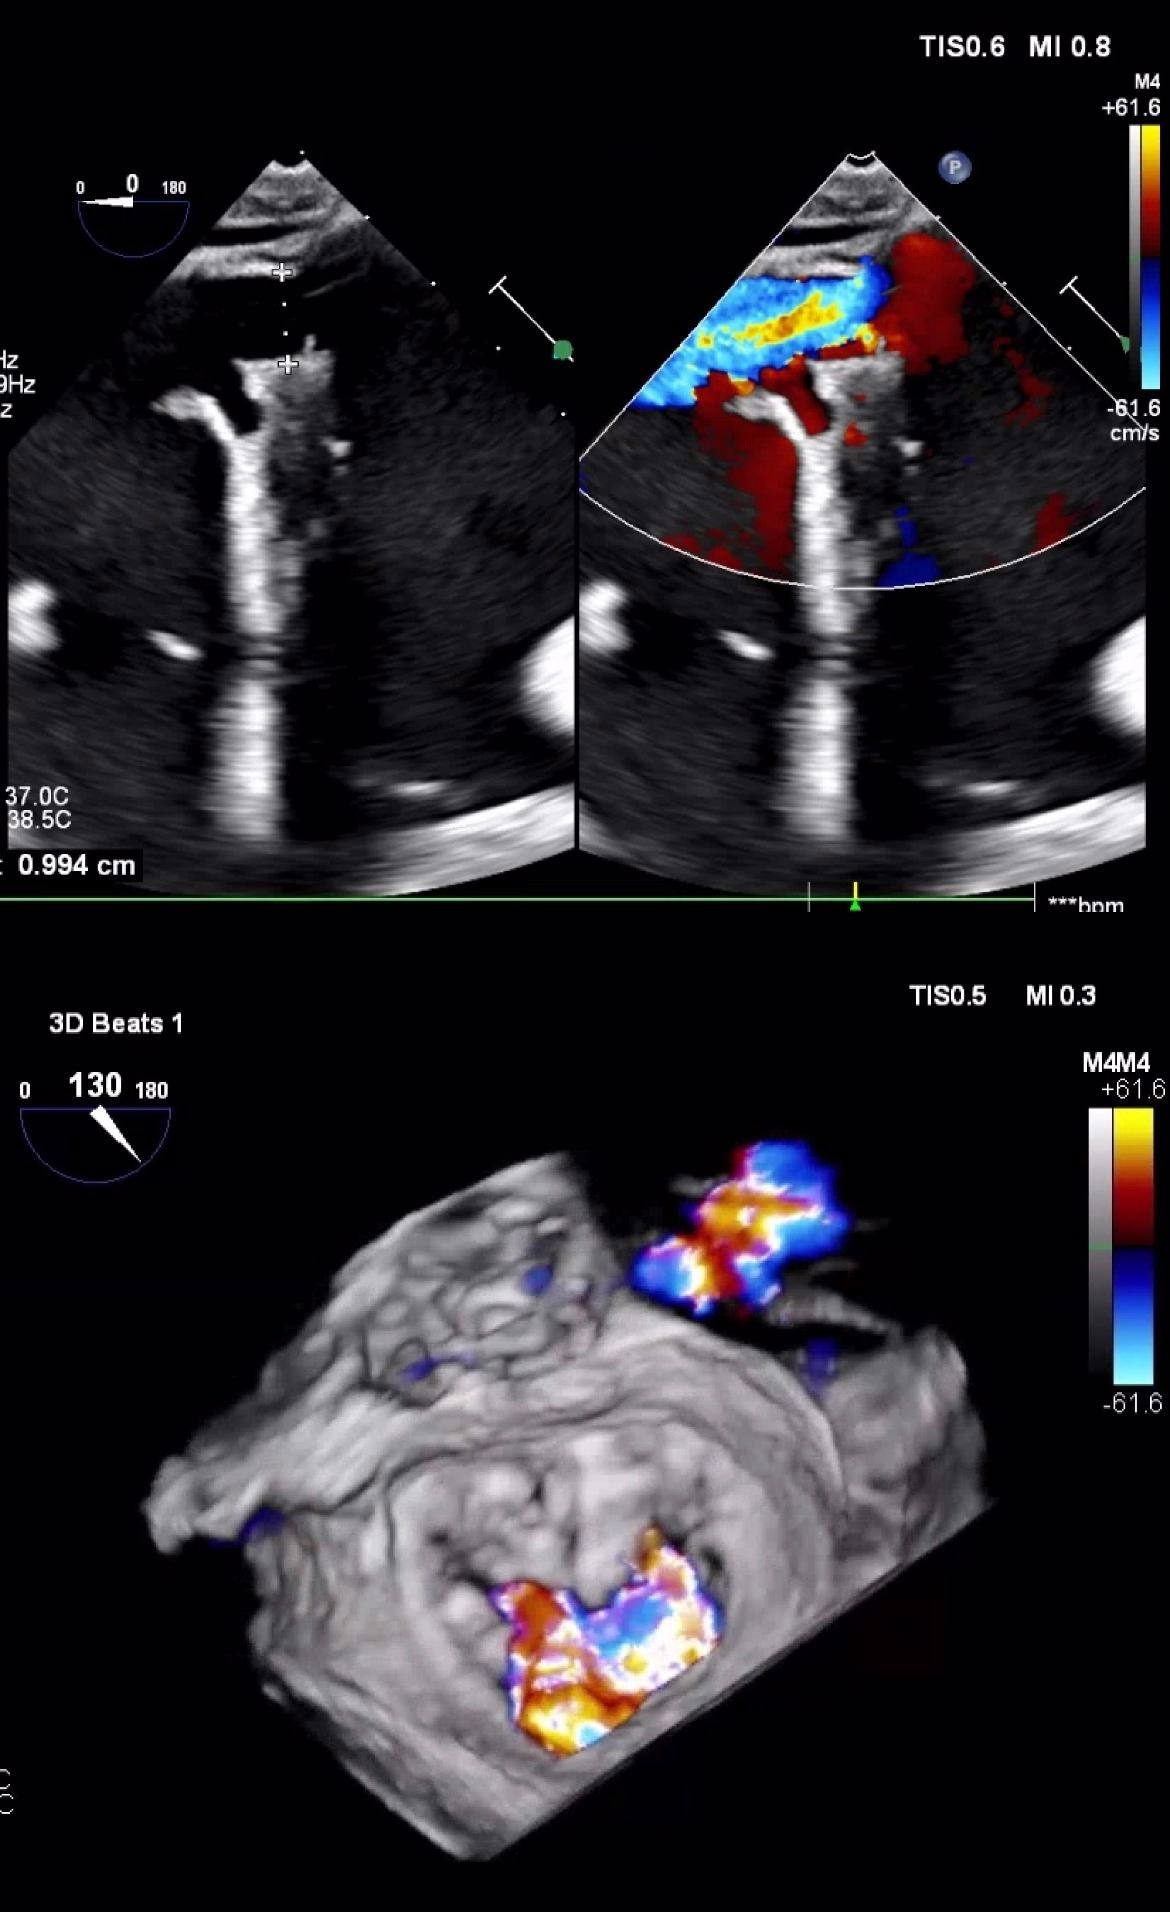

Case presentation: A 76-yo female with hypertension, obesity and asthma presented with progressively worsening dyspnea and mild substernal chest pain for 4 days. She appeared pale, diaphoretic, and hypoxic, with troponin of 22ng/mL and lactate of 9mmol/L. ECG showed Q waves with STE<1 mm in the inferior leads. A bedside EchoCG suggested possible VSR with a L-to-R shunt. Emergent angiography showed a 100% thrombotic occlusion of LCA and chronic 100% RCA occlusion. Right heart catheterization indicated elevated right-sided pressures with a stepwise increase in SaO2 from 45% the RA to 70% in the RV. She remained hemodynamically unstable requiring mechanical ventilatory and circulatory support with intra-aortic balloon pump (IABP) and vasopressors. Transthoracic EchoCG showed LVEF of 30% with akinetic inferior wall and RV, irregularly shaped 1 cm VSD in the mid-inferoseptum with a predominant L-to-R shunt, along with intramyocardial dissection, partially torn papillary muscle with severe MR. The patient was kept in ICU for 25 days with IAPM to allow for scarring of the VSD followed by percutaneous VSD closure with an Amplatzer device and mitral valve repair with a MitraClip. IABP was removed subsequently but the patient failed weaning process and ended up requiring tracheostomy. She was successfully discharged to a skilled nursing facility two months after admission.